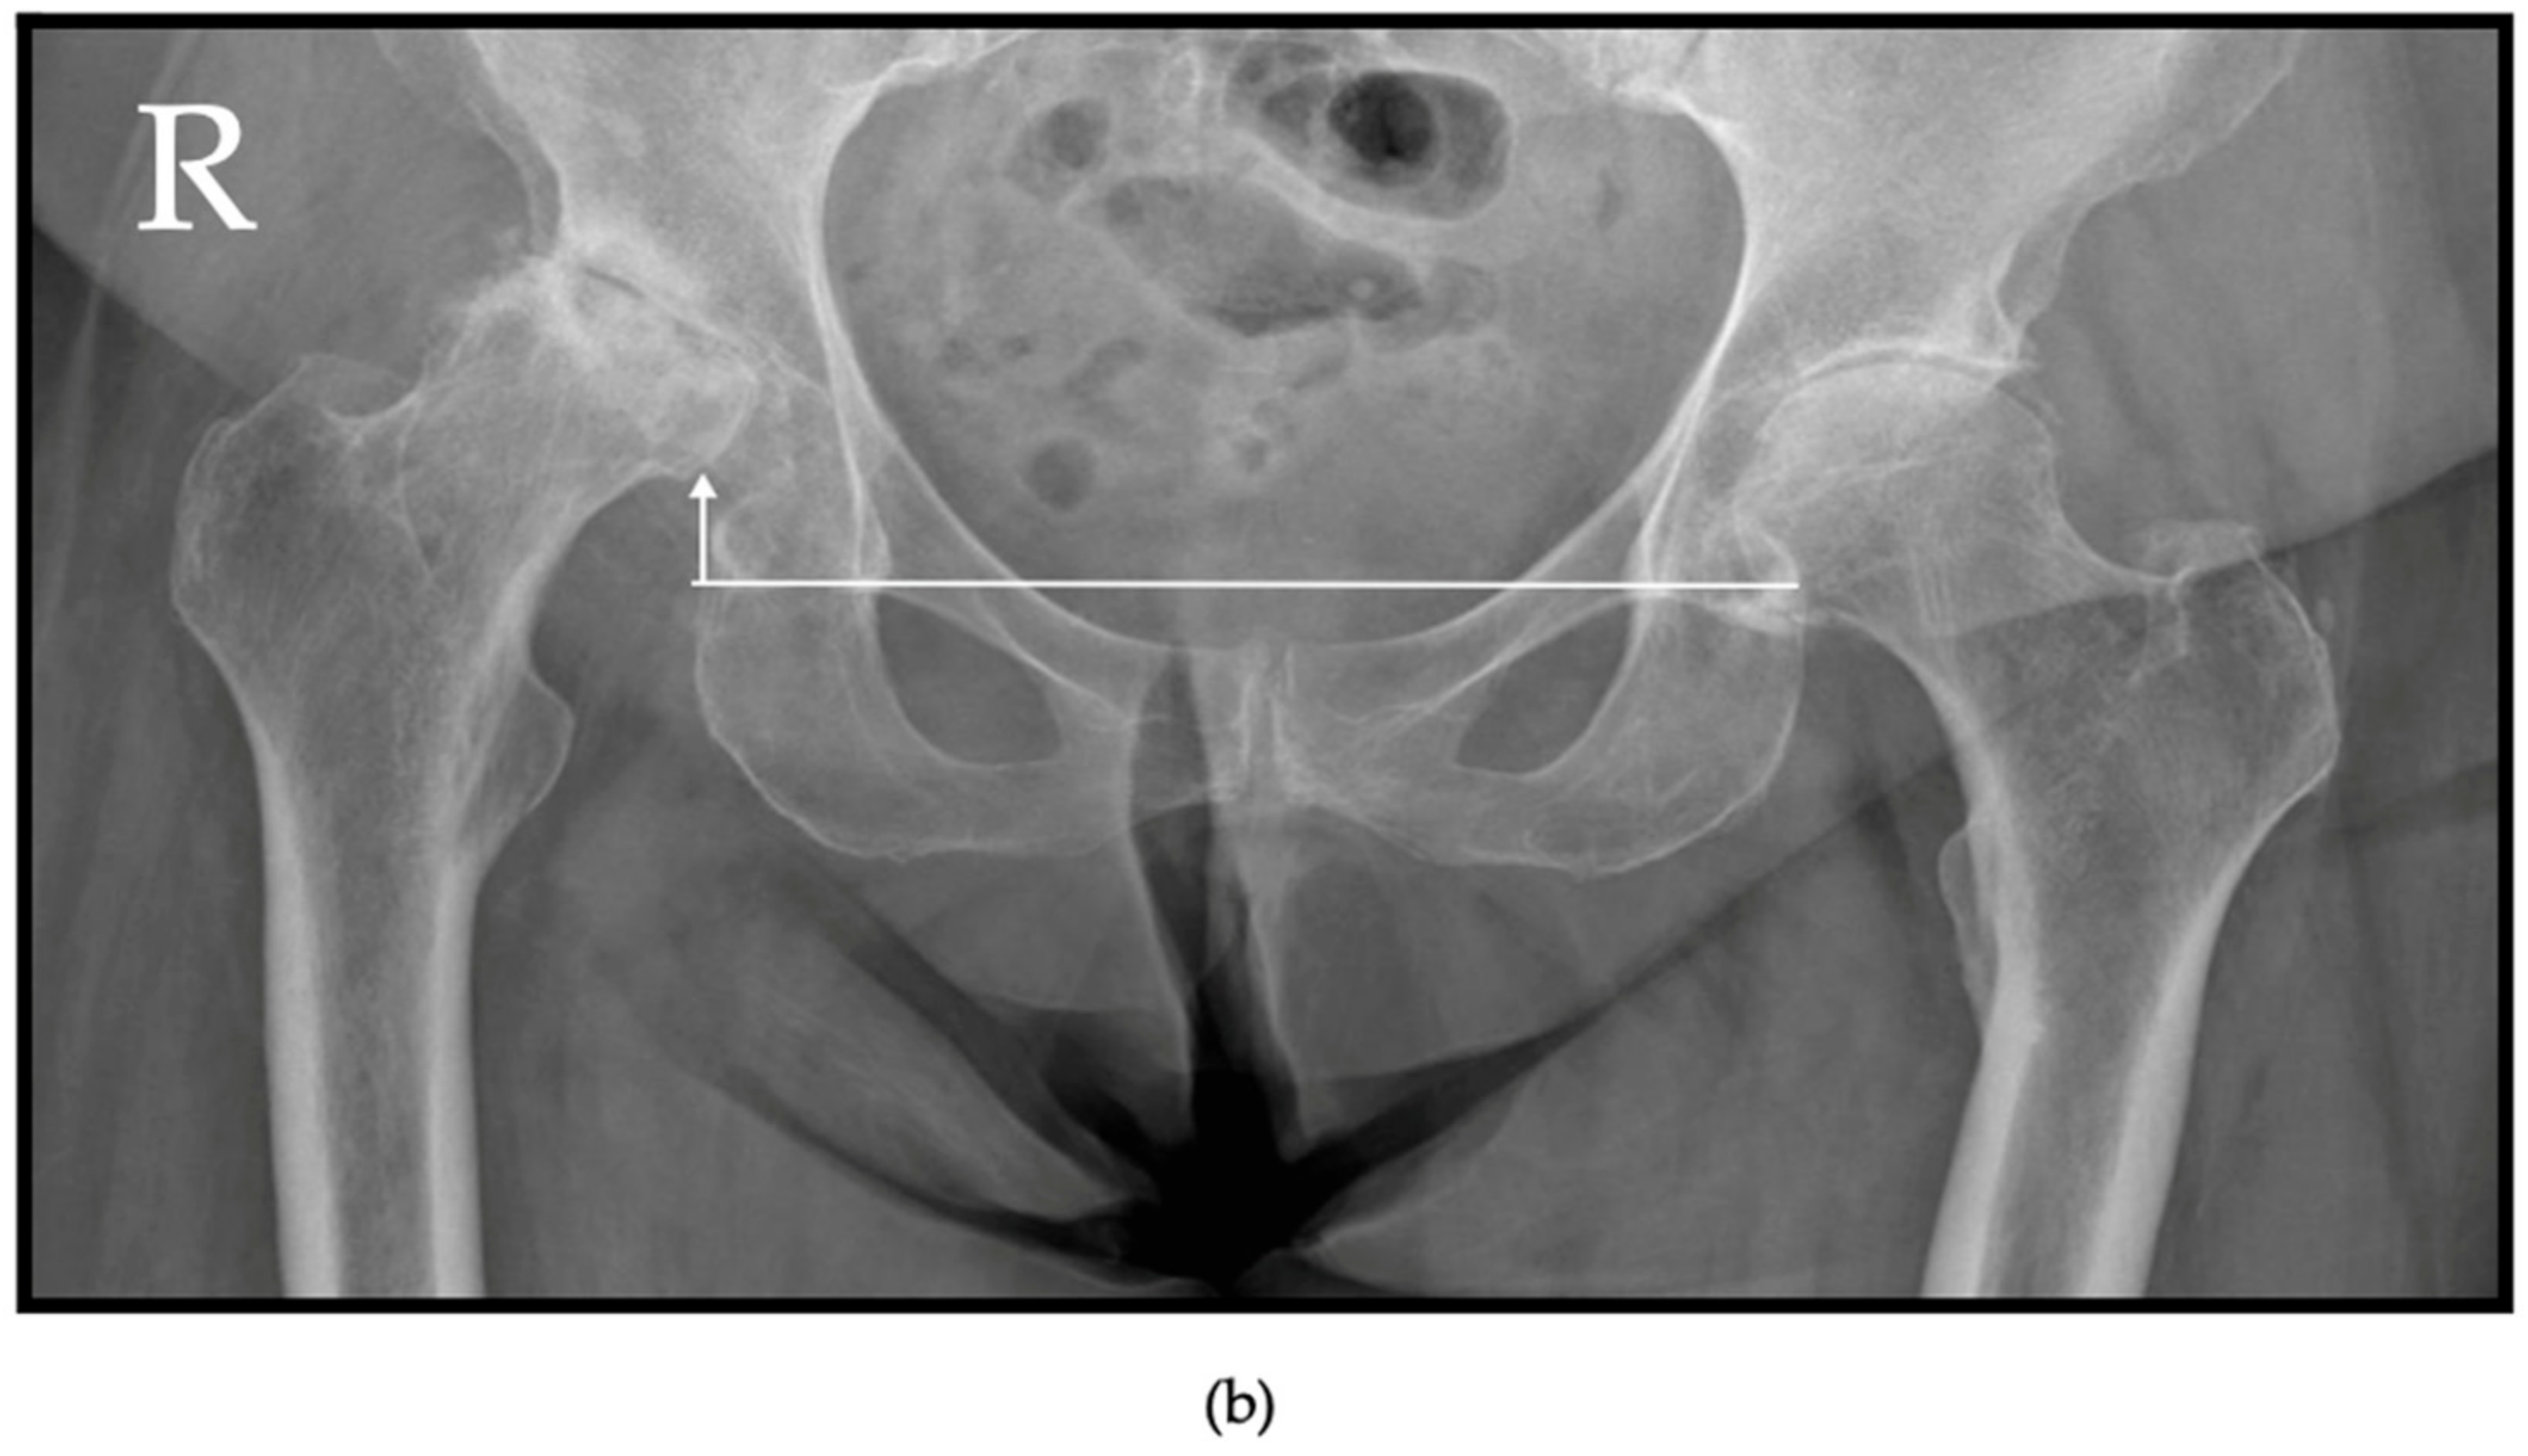

6.1. Radiographs

| Grade II | Complete disappearance of the joint space; deformed femoral head and acetabulum; femoral head ascension ≤ 0.5 cm above radiologic teardrop. | ||

| Grade III | Complete disappearance of the joint space; partial osteolysis of the femoral head; femoral head ascension > 0.5 cm above radiologic teardrop. | ||